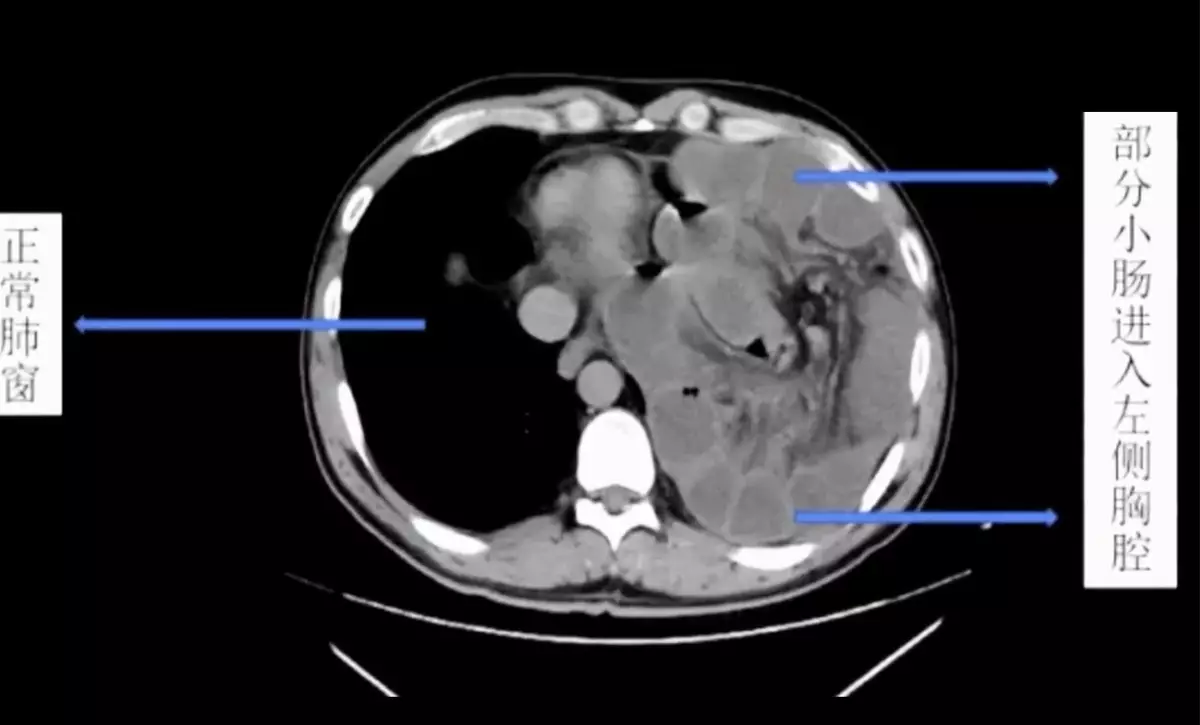

腹腔壓力突然升高或漸升就會造成膈肌破裂,破裂以後小腸就鑽進胸腔近2米。網上截圖

醫院腸胃外科主任邱磊表示:「病患是坐著輪椅來的,腹痛難忍,地方醫院已經替他打了兩隻強力的止痛藥,但疼痛仍無法緩解,到院時已經全身冰涼,雖然神智仍然清楚,但已經出現休克的徵兆,左肺的呼吸聲完全消失」,院方立刻替他進行電腦斷層掃描(CT Scan),「片子顯示左肺已經全都被壓縮扁了,左邊胸腔裡全都是白白的東西」,研判是男子的小腸。

邱磊表示,男子曾罹患結腸癌,當時手術切除掉部分的膈肌(diaphragm),「但修補的部位沒有天生的那麼堅固」,患者經常健身,加上愛喝酒常嘔吐,腹腔壓力變化大,造成膈肌破裂,「長達2米的小腸就從破裂的位置鑽進胸腔」,形成醫學上的「橫膈疝氣」(diaphragmatic hernia,膈疝)。

由於小腸的擠壓,男子左邊的肺已經被頂到嚴重萎縮,小腸堆積充血的結果也導致壞死與內出血,最後經過緊急手術切除,才脫離險境,但原本長約6米的小腸,只剩下約4米。